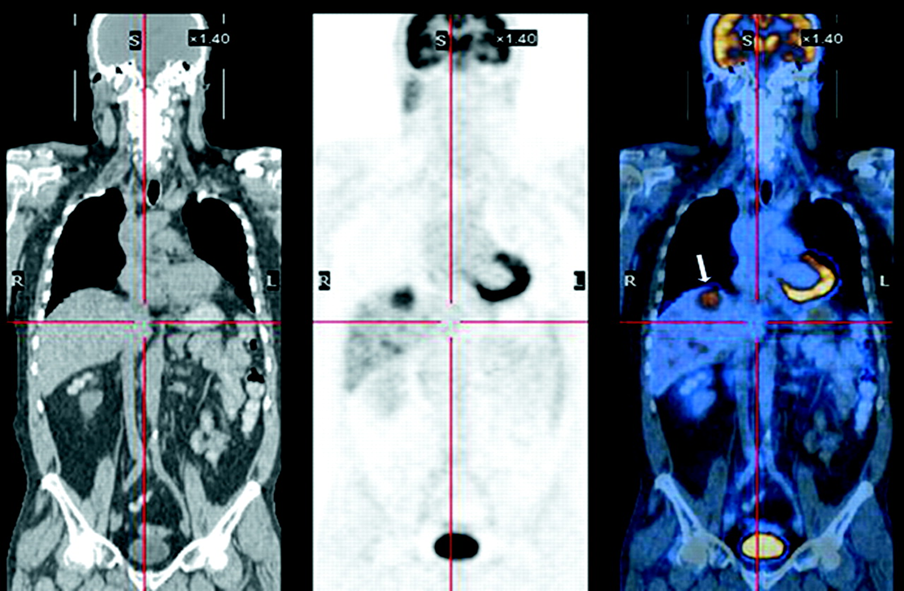

what does this image show

melanoma (diffuse) whole body

melanoma (scale area)